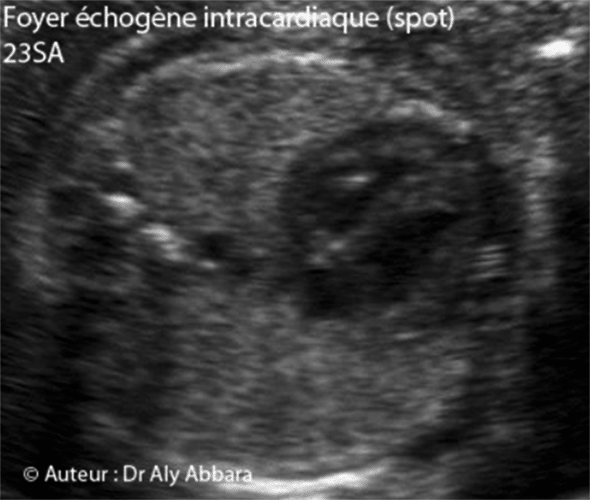

Coeur foetal - Spot intra-cardiaque - 23 SA

• Images échographiques montrant un la présence, dans le ventricule gauche fœtal, un foyer hyperéchogène (spot ou point lumineux - echogenic cardiac focus -ECF ; intracardiac echogenic focus - IEF)

• Le spot intraventriculaire est un foyer ou nodule hyperéchogène (d'une échogénicité égale à celle de l'os) ; il s'agit d'une calcification (minéralisation) du muscle papillaire et d'un pilier valvulaire ; sa taille est habituellement inférieure à 3 millimètre.

• Dans le cas présenté dans cet article, le fœtus est trisomique 13 âgé de 23 SA. L'étude de la morphologie cardiaque approfondie ne révèle pas la présence d'autre anomalie, mais par contre, d'autres malformations majeures ont été mises en évidence : séquence holoprosencéphalie alobaire avec microcéphalie (périmètre céphalique = 170 mm, soit "-3,24 DS") proboscis, cyclopie, arhinie ; une hypoplasie du pavillon de l'oreille externe ; un spina bifida aperta ; une hyperéchogénicité intestinale ; une artère ombilicale unique ; main crispée unilatérale et enfin, un retard de croissance in utero modéré et symétrique.